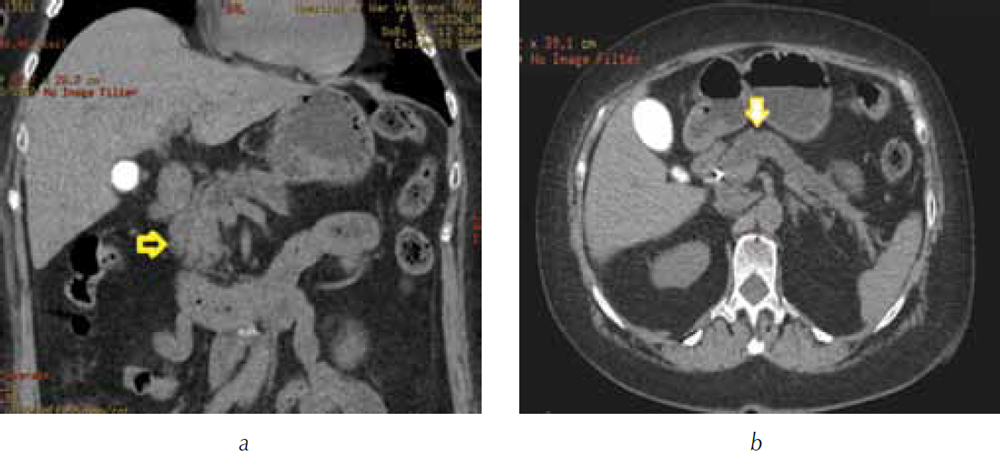

При нативном сканировании опухоль в головке поджелудочной железы не отличалась по плотности от окружающей паренхимы и была не видна. В гепатохоледохе визуализировался стент. Отмечалось расширение главного панкреатического протока в теле и хвосте поджелудочной железы до 9 мм (рис. 1).

Рис. 1. Компьютерная томография гепатопанкреатодуоденальной зоны в нативную фазу сканирования: а — трехмерная реформация в алгоритме MIP. Головка поджелудочной железы однородной структуры (стрелка), опухоль не видна; b — трехмерная реформация в аксиальной проекции. В теле и хвосте поджелудочной железы расширен главный панкреатический проток (стрелка)

В панкреатическую фазу опухоль по степени накопления контрастного вещества не отличалась от окружающей паренхимы поджелудочной железы и также была не видна (рис. 3).

Рис. 3. Компьютерная томография гепатопанкреатодуоденальной зоны в артериальную фазу сканирования: а — трехмерная реформация в коронарной проекции в алгоритме MIP. Головка поджелудочной железы однородной структуры, равномерно накапливает контрастный препарат (короткая стрелка), опухоль не видна. В теле поджелудочной железы расширен главный панкреатический проток (длинная стрелка); b — трехмерная реформация в аксиальной проекции в алгоритме MIP. В теле и хвосте поджелудочной железы расширен главный панкреатический проток (стрелка)